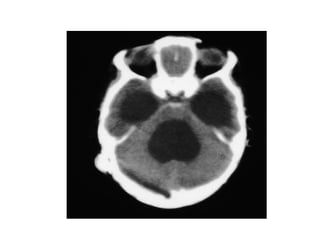

Investigation U ltrasonography to visualize the ventricular system(when the anterior fontanelle is patent). Also for antenatal diagnosis CT and /or MRI of the head; it is important to exclude any abnormal masses and to study the size and the shape of the ventricles, and some time needs contrast study.  LP in cases of communicating hydrocephalus for both diagnostic and therapeutic…..( NPH)

Investigation U ltrasonographyto visualize the ventricular system(when the anterior fontanelle is patent). Also for antenatal diagnosis CT and /or MRI of the head; it is important to exclude any abnormal masses and to study the size and the shape of the ventricles, and some time needs contrast study. LP in cases of communicating hydrocephalus for both diagnostic and therapeutic…..( NPH)